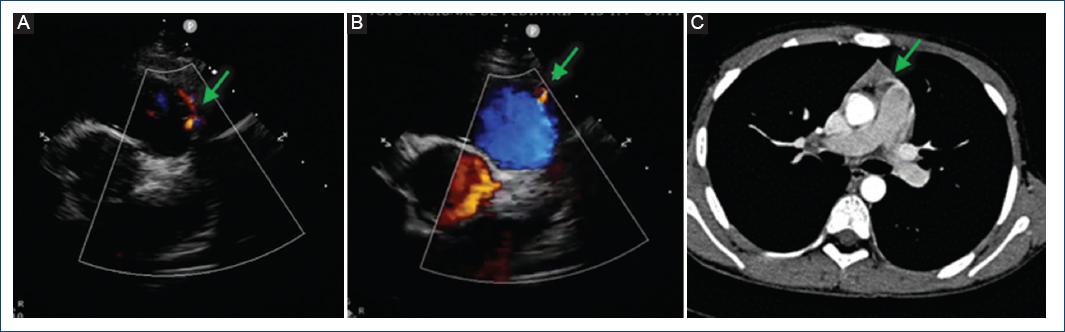

Figura 1 A y B: ecocardiograma transtorácico en el que se observa un flujo continuo retrógrado de 1 mm en la parte proximal del tronco de la arteria pulmonar (flecha). C: angiografía por tomografía computarizada de tórax que muestra un pequeño vaso en la parte anterior del tronco pulmonar, sin lograr determinar su origen ni su trayecto (flecha).

Varón de 11 años al que se detectó un soplo cardiaco a la edad de 8 años por médico pediatra, quien comentó al familiar que este era un soplo «inocente» y se le dio vigilancia por 3 años. Al no modificarse el soplo con el tiempo, es enviado a nuestra institución, asintomático cardiovascular. Exploración física: buen crecimiento y desarrollo, soplo expulsivo II/IV, en mesocardio, tono agudo, timbre piante, sin modificación con maniobras, hígado no congestivo, pulsos normales en las cuatro extremidades, resto de la exploración sin alteraciones. Electrocardiograma y telerradiografía de tórax normales. Ecocardiograma transtorácico con presencia de flujo continuo retrógrado por Doppler color de 1 mm que llega al tronco de la arteria pulmonar, sin lograr determinar su origen (Fig. 1 A y B). La angiografía por tomografía computarizada (angio-TC) de tórax reporta una estructura vascular delgada, elongada, que comunica aparentemente la aorta ascendente con el tronco de la arteria pulmonar (Fig. 1 C). Se propone cateterismo cardiaco diagnóstico. En la angiografía de la aorta ascendente y en coronariografías selectivas se aprecia una fístula coronaria que nace inmediatamente después del ostium de la coronaria derecha, de 1 mm de diámetro, con un trayecto anterior e izquierdo sobre el infundíbulo pulmonar, drenando a la parte proximal del tronco pulmonar por arriba del anillo valvular pulmonar (Fig. 2 A y B), y una segunda fístula con origen en el tercio proximal de la arteria coronaria descendente anterior de 1 mm, drenando de igual forma en el tronco de la arteria pulmonar (Fig. 3 A y B), ambas de 0.15 mm a su llegada al tronco pulmonar. Debido al tamaño tan pequeño de las fístulas, se decide no realizar intervencionismo y continuar la vigilancia.